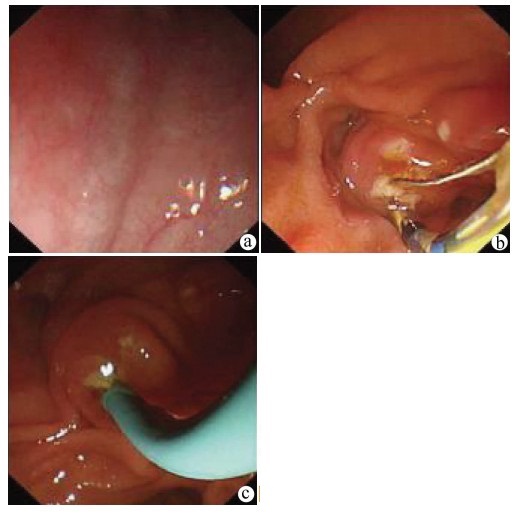

A case of portal biliopathy

Peng JIANG, Shupeng WANG, Yahui LIU

2022, 38(2): 430-432. DOI: 10.3969/j.issn.1001-5256.2022.02.034

Abstract(648) HTML (233) PDF (2686KB)(37)

Abstract: